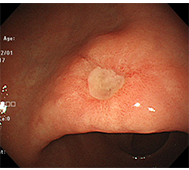

食道がん

- 内視鏡治療 :病変がリンパ節転移の無い早期食道がんに対し、内視鏡治療が行われます。